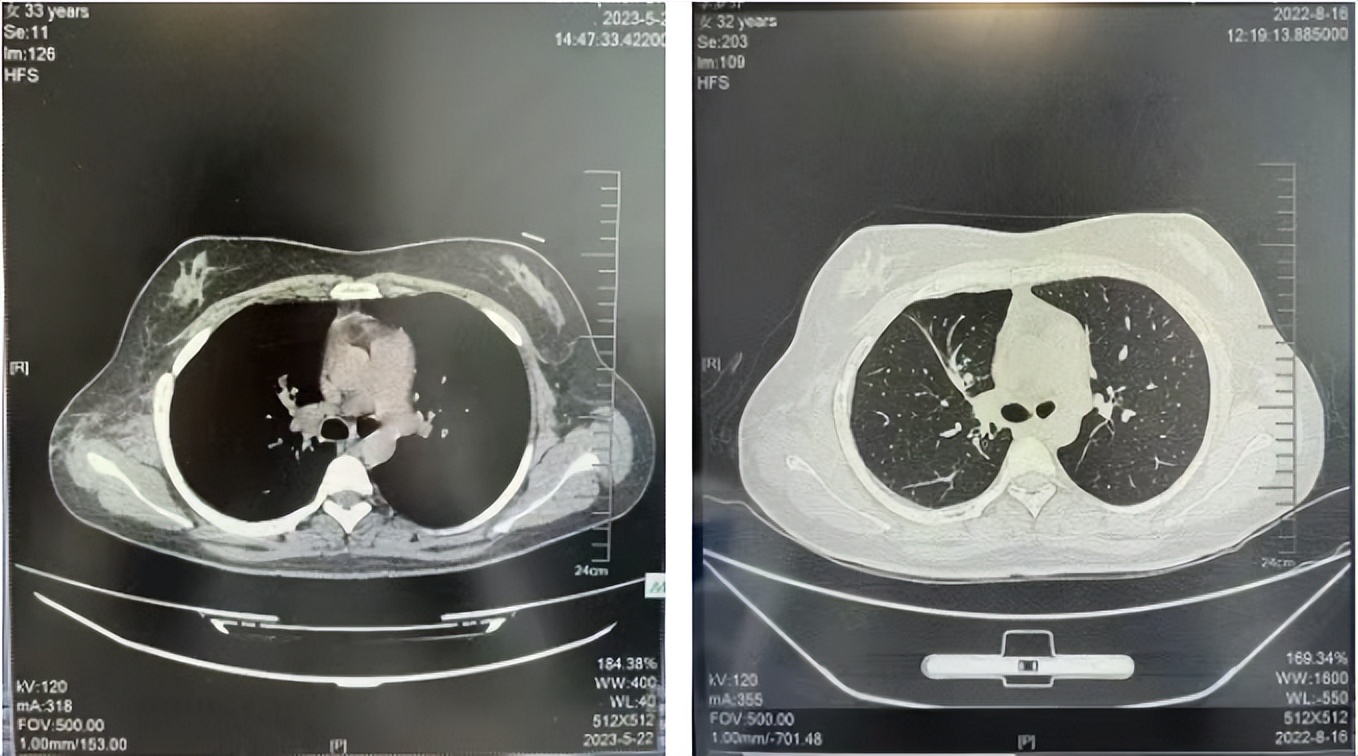

2016年1月复查CT提示支气管截断可见新发小结节,一线治疗采用培美曲塞+DDP方案化疗4周期(培美曲塞3.36,DDP 480mg)。化疗后复查胸部CT:右肺见不规则结节样影,最大层面大小约19mm*8mm,较前比较明显增大,疗效评估PD。2017.3-2017.4予单药多西他赛化疗3周期,疗效评估SD。2018年5月末复查CT提示结节较前增大,评效为PD,2018年6-10月予多西他赛+CBP化疗4周期,疗效评估SD。2022年5月患者出现活动后气短,复查胸部CT示右肺膨胀不良;右侧胸腔积液增多。胸腔积液包埋病理示符合肺腺癌细胞。行NGS基因检测:EML4:exon13-ALK:exon20融合。PD-L1(克隆号22C3)TPS<1%。

2022.08

2023.05

2024.12